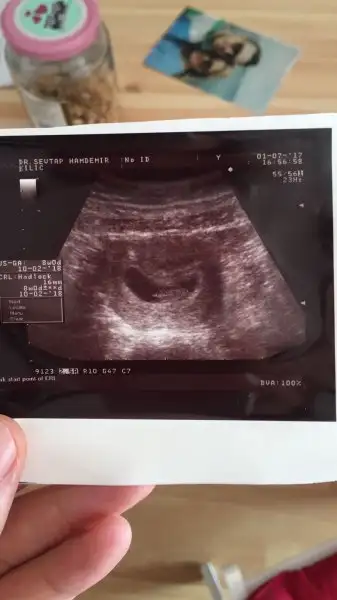

erkek galiba solunda herhalde topigi yanlis anlamadi isem7+1 sizce cinsiyet nedir?

Canım ben erkeğe benzettim bu Ramzi teorisine göre allah gönlüne göre sağlıklı sıhhatli bi evlat nasip etsin inşbenim minigime de bakar misiniz acaba

ck sagoll canmm. allh herseyin hayrlisini versin. onceligim tabiiki sahlikli olmasi ama insan yinede merak ediyorr.Canım ben erkeğe benzettim bu Ramzi teorisine göre allah gönlüne göre sağlıklı sıhhatli bi evlat nasip etsin inş

Çok teşekkür ederim. Sağlıkla sıhhatle gelsin. Bu da 7 haftalık karından usg kız mı acaba gerçektenKız gibi canım Rabbim sağlıklı sıhhatli hayırlı evlat nasip etsin